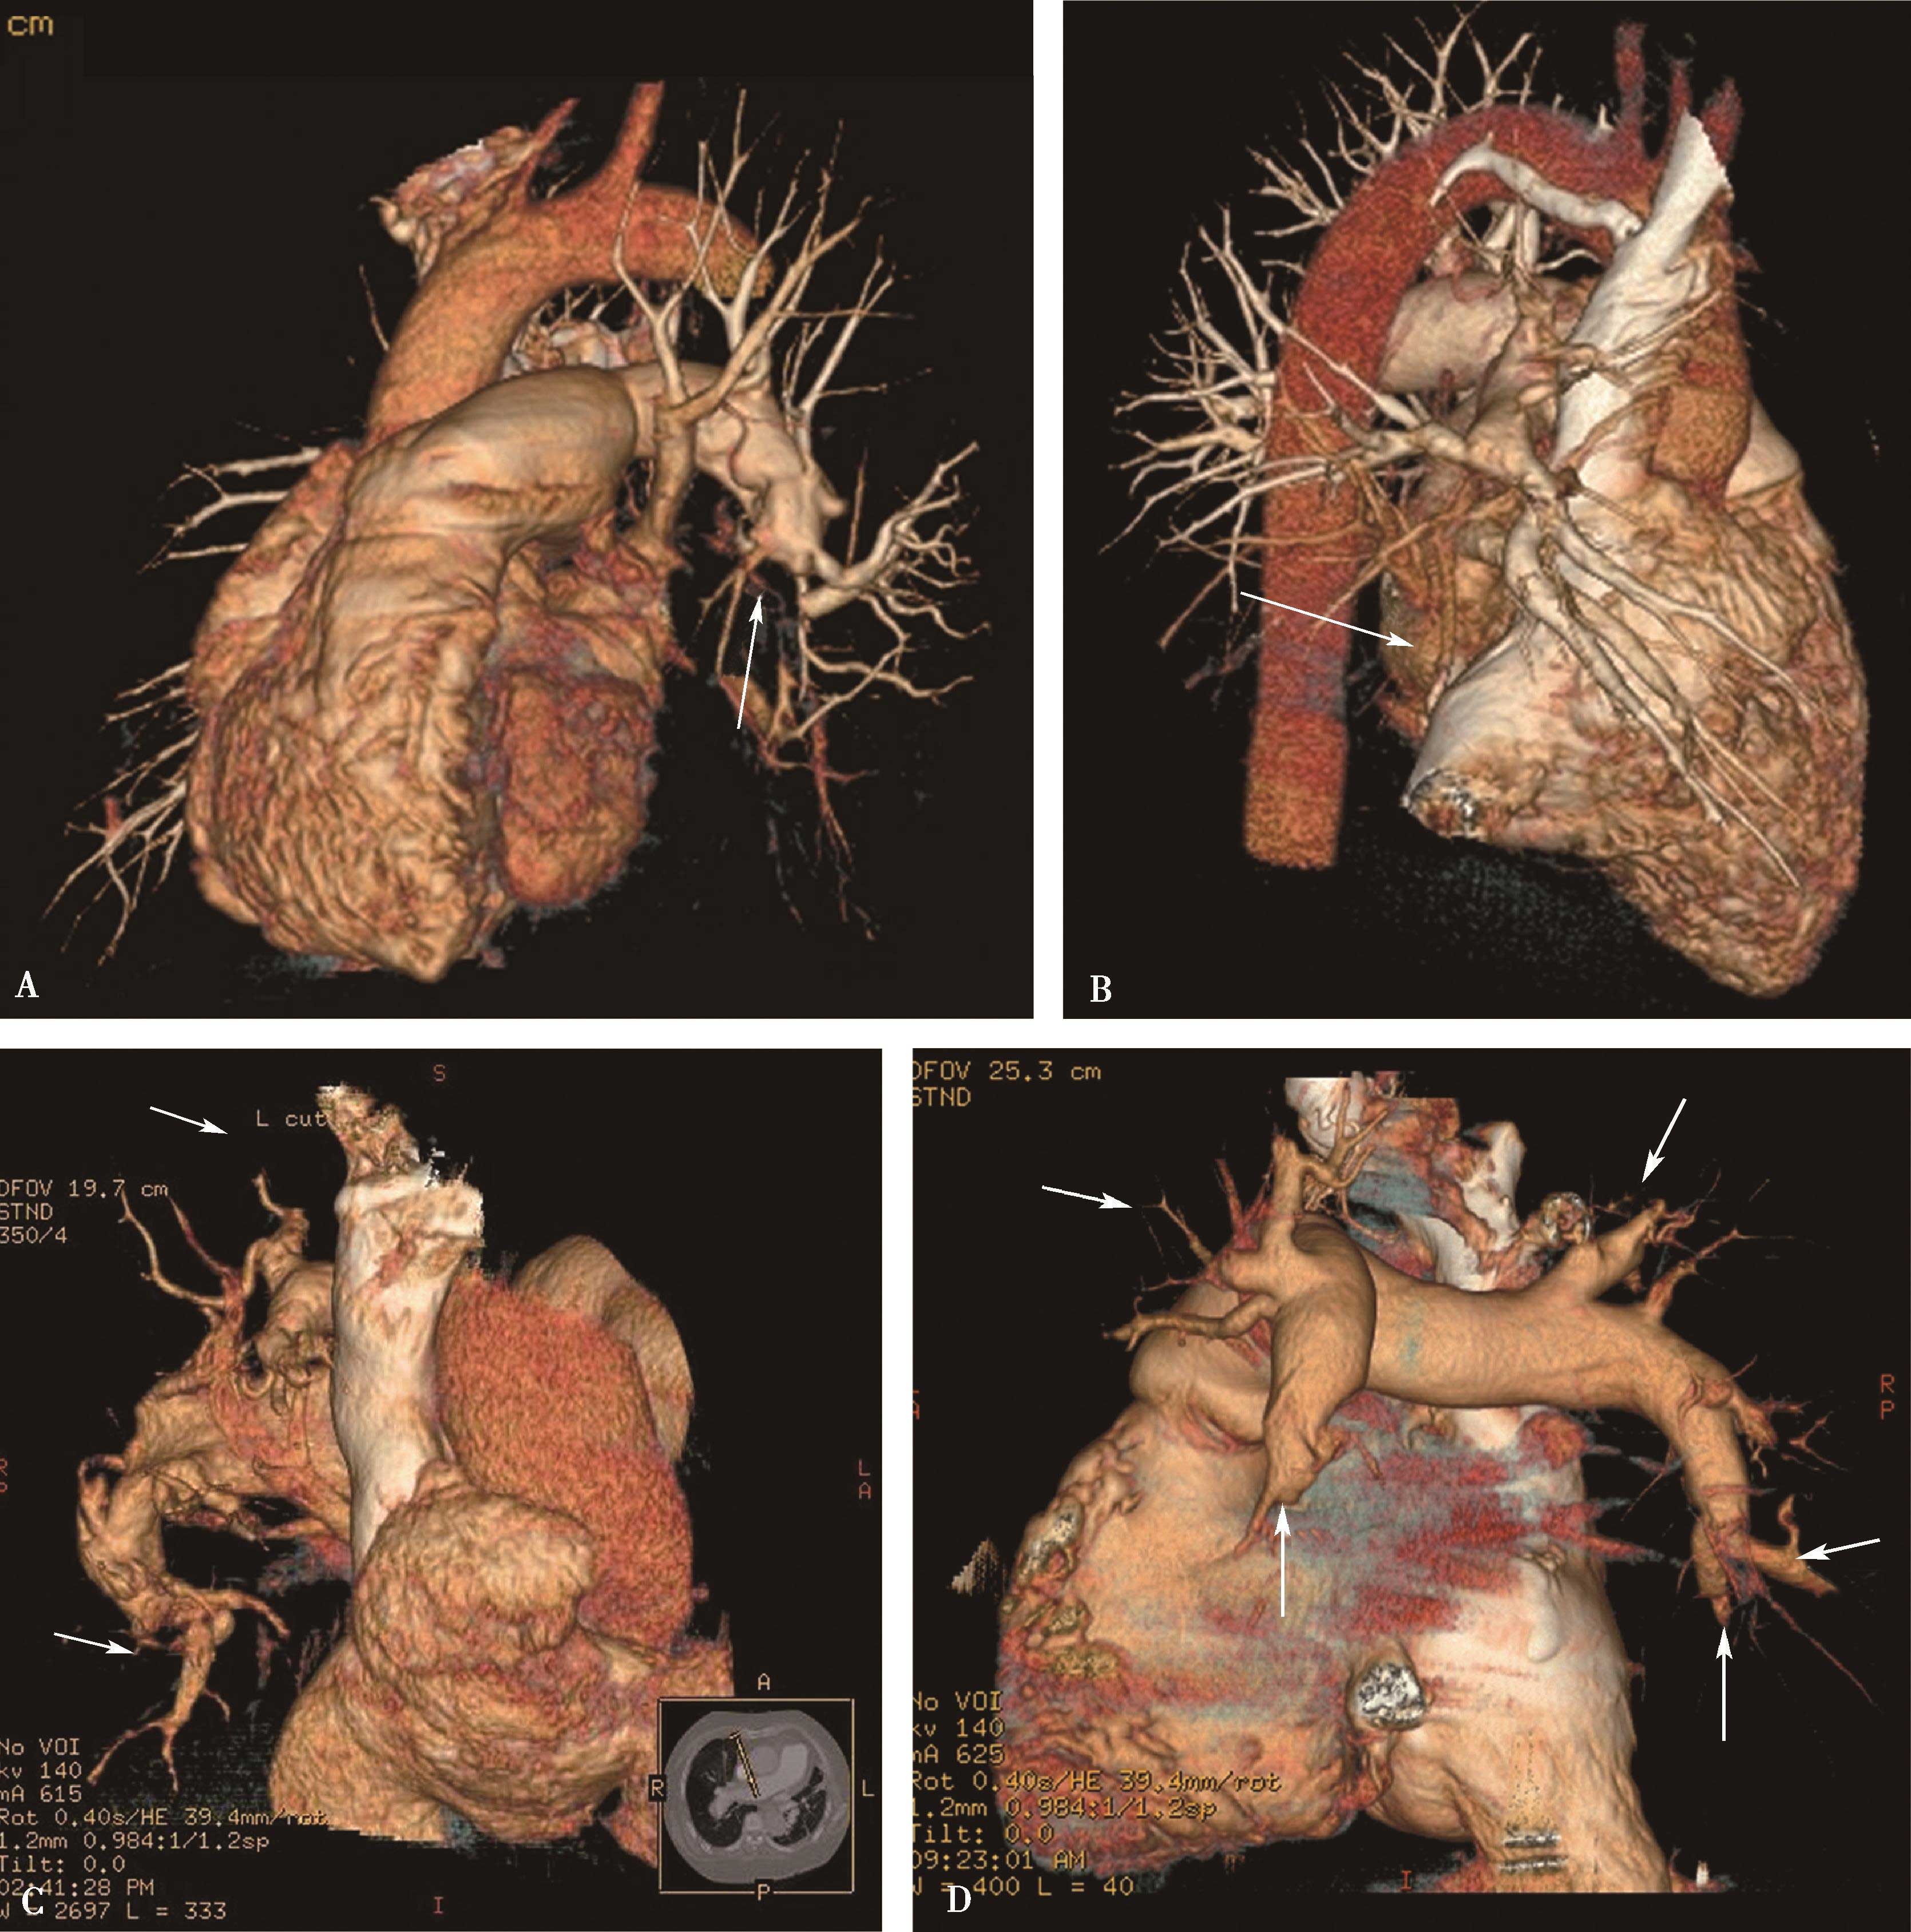

1)主肺动脉干或/和左右肺动脉干梭形瘤样扩张,腔内不同程度附壁血栓(图8-5-4)。

图8-5-4 反复发作口腔溃疡,临床诊断白塞病

横断图像。A~C.主肺动脉、瘤样扩张,左右肺动脉瘤样扩张,不规则附壁血栓(↑);D~F.三维重建主肺动脉及左右肺动脉瘤样扩张,红色为附壁血栓(↑),波及肺叶分支;CT诊断:肺动脉瘤累及主肺动脉、左右肺动脉及叶分支,附壁血栓形成,病变性质考虑为白塞病

2)肺动脉叶段分支瘤样扩张,真性或假性动脉瘤形成,腔内不同程度附壁血栓(图8-5-5)。

(2)多层重组(MPR)或曲面重组(CPR):

以不同层面、不同角度重建各支肺动脉影像,显示血管病变(动脉瘤)特点、程度、累及范围及附壁血栓特点。

(3)三维重建:

容积再现(VR)或表面阴影显示(SSD):直观显示肺动脉解剖、动脉瘤累及范围。

图8-5-5 男,28岁,反复口腔及生殖器溃疡5年,白塞病,肺动脉瘤

A.胸部X线片,示左右肺动脉瘤(↑);B.横断图像,左、右下肺动脉动脉瘤形成,附壁血栓形成(↑);C.多层重组(冠状位)示右下肺动脉动脉瘤合并附壁血栓(↑);D.多层重组(左前斜位)示左下肺动脉瘤合并附壁血栓形成(↑)。CT诊断:左右肺动脉瘤,附壁血栓形成,病变性质白塞病